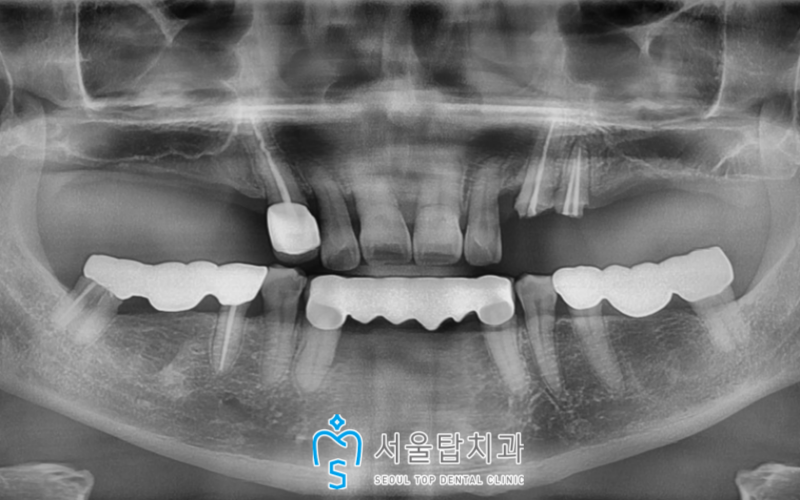

파노라마 사진을 촬영하여

치료계획을 수립해보았습니다!

🦷 왼쪽 위 🦷

치아머리가 부러진 송곳니(#23)와

첫 번째 작은 어금니(#24)는

발치 후 기존 상실된 부위와 함께

임플란트 식립을 계획하였습니다.

🦷 오른쪽 위 🦷

기존 상실된 부위로,

임플란트 식립을 계획하였는데요.

큰 어금니가 식립되는 자리에는

잇몸뼈가 너무 부족하여

상악동 거상술 + 뼈이식을 동반한

수술이 필요하였습니다.

🦷 치료전 🦷